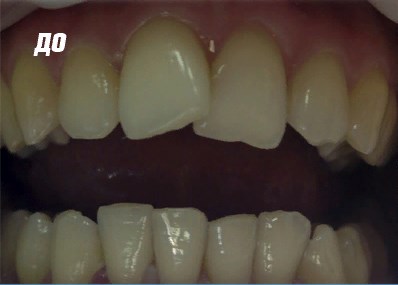

Работы врача

Фото ДО

Фото ПОСЛЕ

Наведите для просмотра

Реставрация фронтальной группы зубов